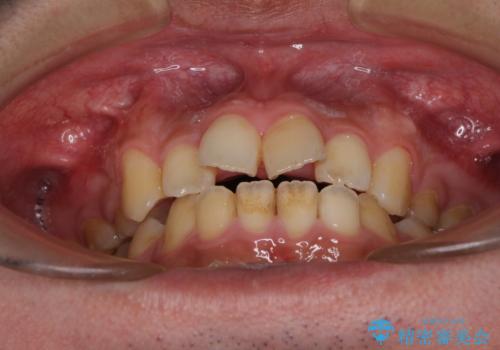

後戻りでデコボコの前歯 インビザライン矯正治療

- 高校時代に行った抜歯矯正が後戻りをしたとのことで来院された患者様です。

再矯正であることから、目立ちにくい装置を希望されたため、インビザラインにて矯正治療を行うこととしました。

下顎骨が左側に変位しているため、正中が合わないことは予想できましたが、歯列が整った後も咬み合わせが安定せず、咬み合わせを落ち着かせるために1年以上の期間を要しました。